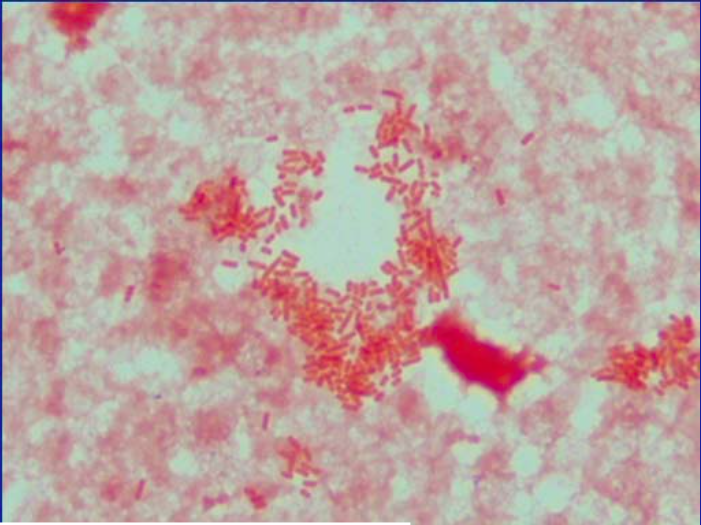

What are Acid Fast stains used for?

They are used for bacteria with cell walls of long chains of fatty acids

What are examples of bacteria that Acid Fast stains?

Auramine-Rhodamine stains…

Mycobacteria